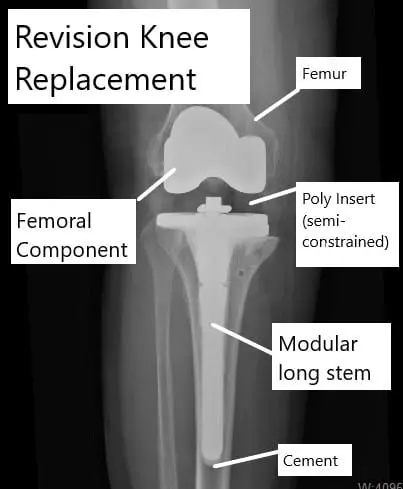

Revision knee replacement showing use of semi-constrained components.

Constrain is the ability of the implant to provide stability in forward-backward and side-to-side motion. The constrained implants are needed in the face of bone loss or labor of the ligaments. Implants may be non-constrained, semi-constrained, or fully constrained depending upon the amount of stability they provide.

During revision surgery, at times there may be an excessive bone loss that may warrant a modular constrained implant. Similarly, in patients with excessive ligament laxity, a constrained implant may be necessary to provide stability. Patients suffering from some kinds of tumors of the bone may require removal of the stabilizing structures of the joint along with the bone tumor. These patients may also require constrained implants.

The constrained implants come in different designs. The originally used hinged constrained implant has been largely superseded by a rotating constrained implant. In a hinged knee replacement implant, there is a connecting rod in between the femoral and tibial components.

The connecting rod has a hinge mechanism to prevent overextension of the joint. This design only allows forward and backward motion and prevents any side to side and rotating motion.

The loss of side to side and rotating motion puts additional stress at the bone-implant interface and may lead to implant loosening or periprosthetic fracture. The rotating constrained implant additionally allows rotating motion about the prosthetic hinge. The hinge is located near the femoral component and a rotating platform is attached to the tibial plate.

The rotating action helps to distribute the stresses more evenly during motion while maintaining stability in the face of bone loss or ligament laxity. The hinged implants are primarily used in revision surgeries and in complex primary knee replacement surgery involving severe deformity or tumors, or salvage surgeries, etc.

The hinged knee replacement implants are also modular that allows the addition of metal wedges or triangles to compensate for bone loss. The stem modularity also allows the addition of long stems to provide stability.